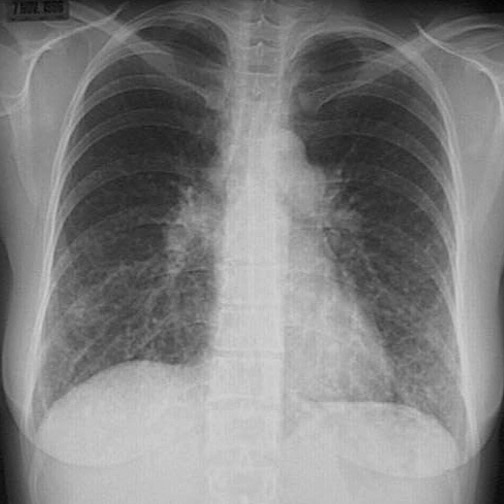

This chest radiograph demonstrates a diffuse finely nodular pattern resulting from multiple small metastases to the lung from a colonic adenocarcinoma. This radiograph was taken at the time the patient became symptomatic.